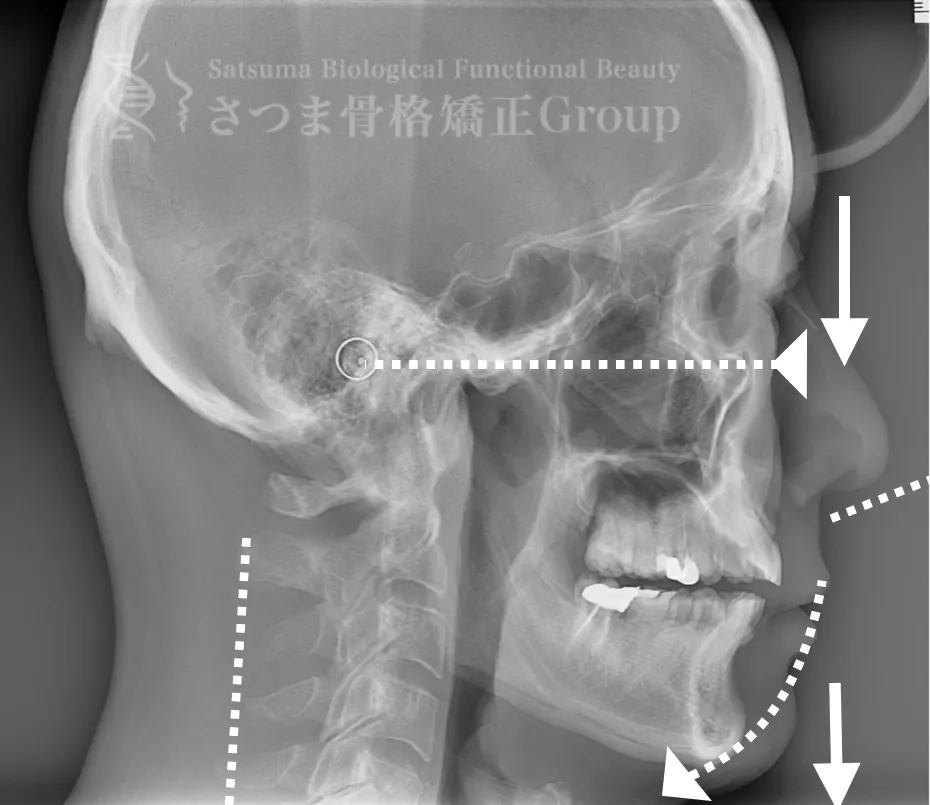

下顎の後方回転あり。 中顔面が伸びて下方に落ちる。 中顔面の奥行きを失っている。 頚椎ストレートネック。 重度の首凝り

Posterior rotation of the mandible The midface is elongated and has dropped downward Loss of depth in the midface Cervical spine straightening (straight neck) Severe neck stiffness

AFTER(マウスピース使用時)

整骨後、形成したマウスピースで形と顎関節の前方回転を誘導。上部頸椎のリリースを促進し、自家矯正力が働きやすいように誘導。蝶形骨口蓋縫合と蝶形骨上顎縫合をモビライゼーションし、可動をブーストし中顔面を短縮。

重度の肩凝りも軽減

After the osteopathy, the custom-formed mouthpiece guides the shape and promotes forward rotation of the temporomandibular joint.

It facilitates the release of the upper cervical spine and encourages the body’s natural self-correcting ability.

Mobilization of the sphenopalatine suture and the sphenomaxillary suture boosts mobility and shortens the midface.